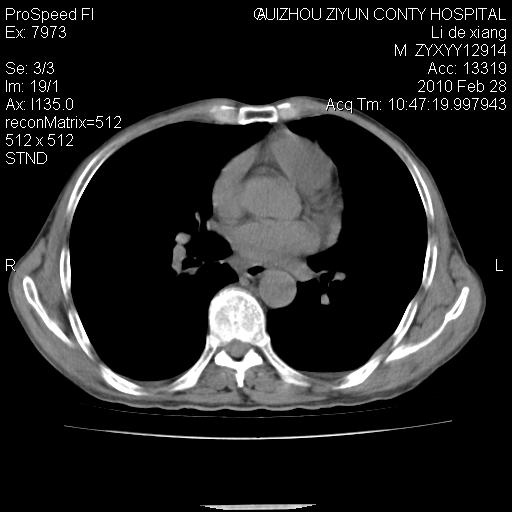

标题: CT24776:男 71Y 咳嗽咳痰胸痛两月,伴声音嘶哑。 [打印本页]

标题: CT24776:男 71Y 咳嗽咳痰胸痛两月,伴声音嘶哑。

左侧中央型肺癌伴左肺上叶阻塞性肺炎及节段性不张可能性大,建议纤支镜检查!

左侧中央型肺癌伴左肺上叶阻塞性肺炎及节段性不张可能性大,建议纤支镜检查!纵隔淋巴结转移.

左侧中央型肺癌伴左肺上叶阻塞性肺炎及纵隔淋巴结转移。

左肺门部肿块,伴左上肺斑块影,周边模糊,支持左肺中央型肺癌伴节段性不张及阻塞性肺炎,结合支气管镜检查。

患者有声音嘶哑,若时间长了,没改变,喉镜检查无异常,可考虑左侧喉返神经受累,因为:左侧喉返神经绕主动脉弓或肺动脉韧带的主动脉端,沿气管与食管之间的沟上行至颈部.

支持肺癌.

左上叶支气管狭窄,阻塞性病变,肺门肿块,纵隔及肺门淋巴结增大,中央性肺癌

左肺中央型肺癌并阻塞性改变、纵膈 淋巴结转移

左侧中央型肺癌伴左肺上叶阻塞性肺炎及纵隔淋巴结转移

支持 左肺中央型肺癌伴左肺上叶阻塞性肺炎,纵隔淋巴结转移。